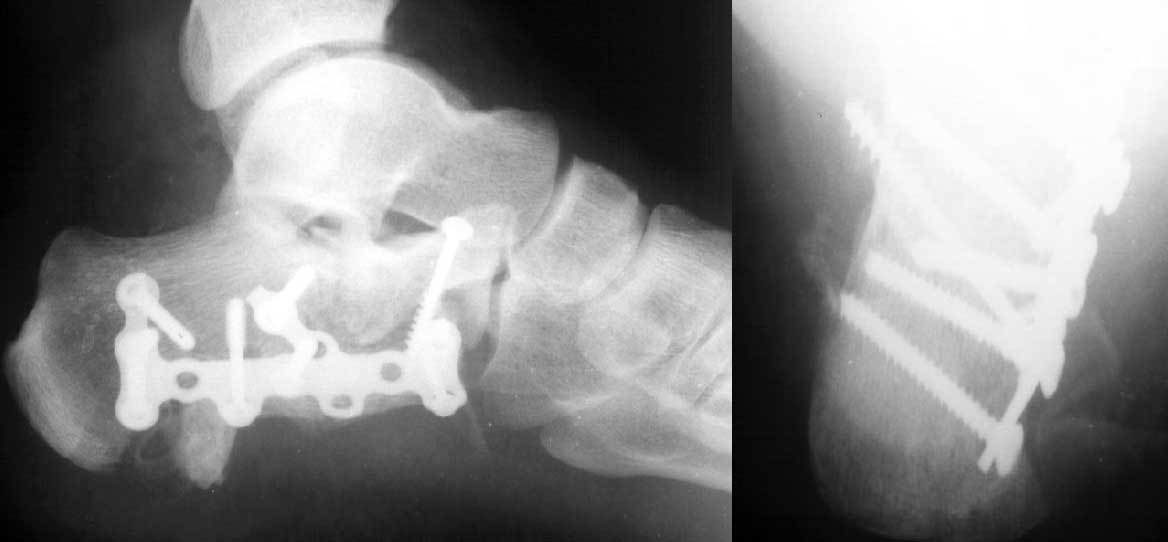

На этой неделе оперировали. КТ наши рентгенологи сделали зачем-то горизонтальной плоскости, поэтому не привожу. Сделали открытую репозицию, заполнили дефект трансплантатом из крыла подвздошной кости.

После удаления спиц положение фасетки немножко ухудшилось. Такие дела. Жду комментариев.

Судя по вашим рентгенограммам, восстановить суставную поверхность таранно-пяточного и пяточно-кубовидного сустава полностью не удалось, хотя угол Белера выглядит гораздо лучше, чем на предоперационной рентгенограмме,

что решает проблему посттравматического плоскостопия, восстановлена длина пяточной кости. Жаль, что возникла проблема с качеством томогафии. Интересно было бы знать, на сколько фрагментов была *расколота* суставная фасетка

В данном случае восстановлена лишь ось пятки - угол Белера в боковой проекции и смещение кнаружи и по длине в прямой. Гораздо проще и с несравнимо меньшим риском этого можно остигнуть, применив внешний остеосинтез.

Там еще и весьма солидный дефект, образовавшийся после репозиции, заполнен трансплантатом.